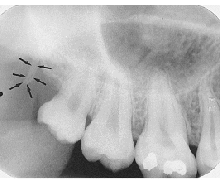

Anterior Nasal Spine

v-shaped radiopaque area at base of nasal septum

(radiopaque)

Inferior Nasal Conchae

diffuse radiopaque projection in the nasal cavity

Maxillary Sinus

radiolucent area located above the apices of the premolar/molar areas in maxilla

(radiolucent)

Maxillary Tuberosity

radiopaque bulge distal to last tooth on max arch

Hamulus

radiopaque pointy projection located distal to max tuberosity

Zygomatic Arch

J or U shaped radiopaque area superior to the maxillary 1st molar region

What surrounds the maxillary sinus?

septa

What appears in the area of the maxillary canine and premolars?

inverted-y

(radiopaque, upside down y)